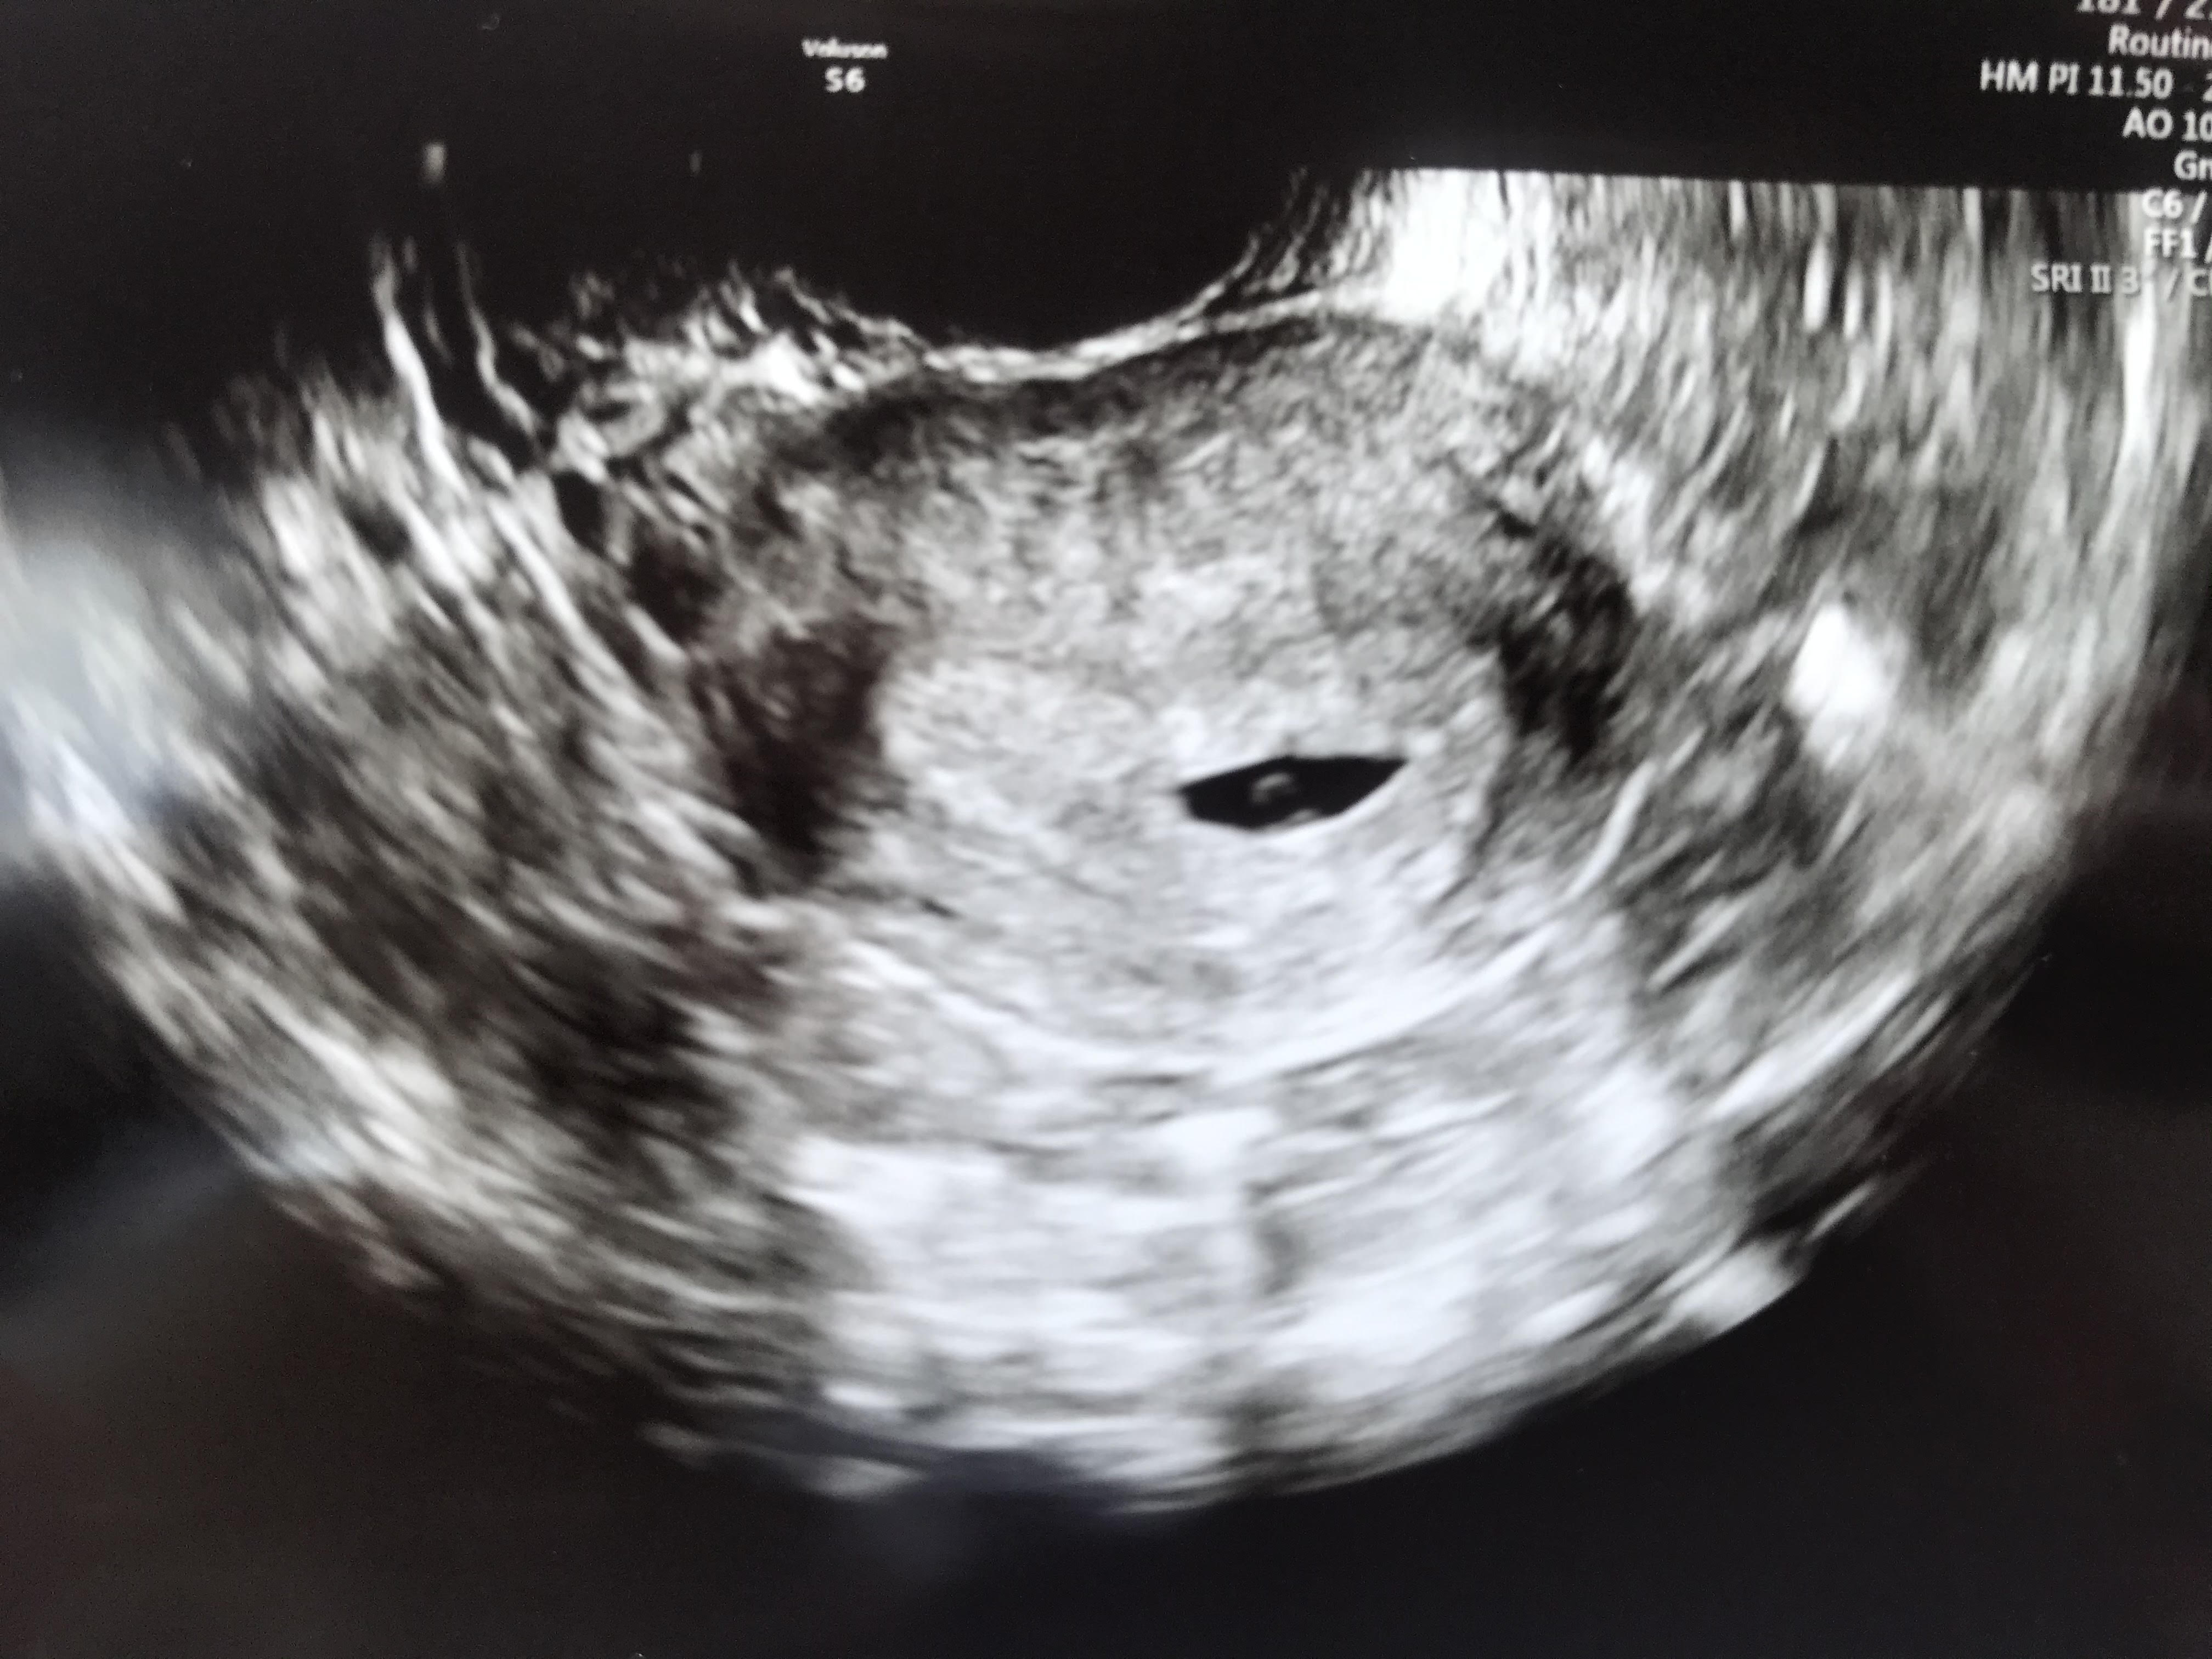

U mnie dokladnie to samoJa też po wizycie, pęcherzyk ciążowy i zoltkowy są, a dzisiaj 5+5. Za dwa tygodnie kolejna wizyta i (mam nadzieję) serduszko - najgorsze dwa tygodnie, nie wiem jak wytrzymam [emoji2368]

W takim razie musimy myśleć pozytywnie i cierpliwie czekać, choć doskonale wiemy że nie jest to takie łatwe. Moja Pani Ginekolog powiedziała że mam się nie stresować i spokojnie czekać [emoji2368]U mnie dokladnie to samo [emoji2368]

Brakiem zarodka się nie przejmuje, bo wiem, że to normalne, bardziej martwi mnie ten bolący jajnik. Mam nadzieję, że torbiele się wchłoną, że nie okaże się pozamaciczna przy okazji wewnątrzmacicznej. Za tydzień w poniedziałek kolejna kontrola i ponownie zmierzy cysty i na tej podstawie zadycyduje co dalej. Liczę na to, że wszystko będzie dobrze![]()